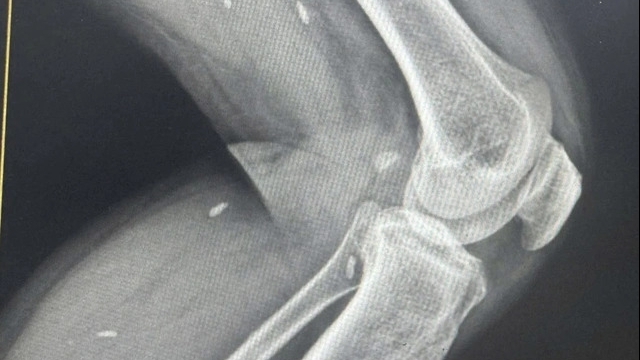

| Vụ ngộ độc ở Long Biên đã khiến bệnh nhân nhập viện, phải đặt nội khi quản, thở máy, lọc máu (Ảnh: BVCC) |